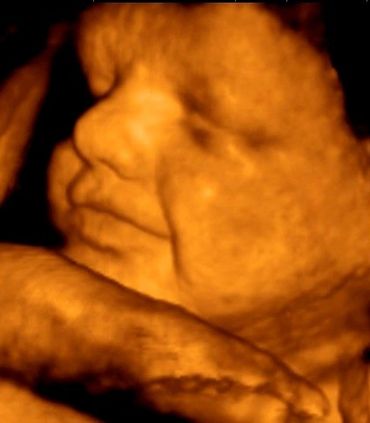

All our providers do their own ultrasounds in the office during your visit. We are known for our ultrasounds and do at least four with each pregnancy. And we can record your ultrasound on a USB device for you to take home and share!